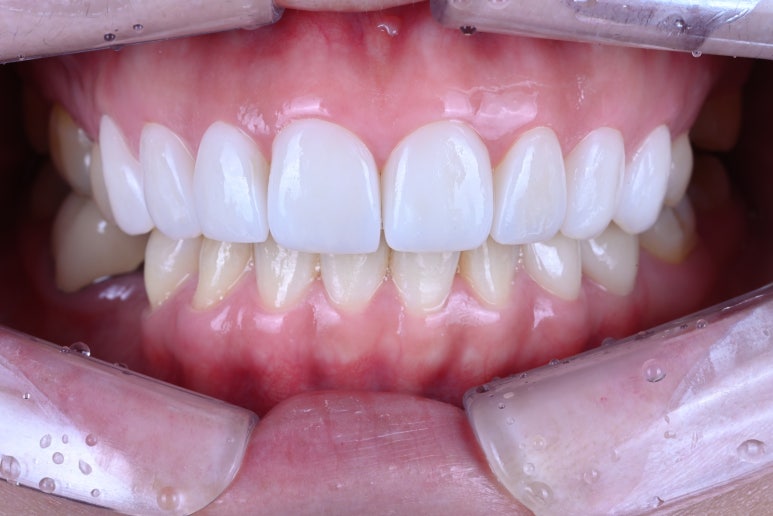

그리하여 완성된 레브네이트 엑스퍼트..

화사한 색감이 생겼습니다.

그리고 도자기처럼 반딱거리는 인공적인 느낌이 아니라, 표면에 세라믹 가공을 첨가하여 약간의 텍스처를 부여한 덕에 자연스러움까지 추가되었습니다.

뭔가 밝아지긴 했는데... 하얘진건 맞는데 자연스럽다는 것..

어디에서 보아도 원래 치아의 어두웠던 색상은 보이지 않고,

치아가 너~무 말 이빨처럼 커보이지도 않고, 자연스러운 생김새를 갖고 있습니다.

아래 치아와 비교해보시면 더욱 더 뚜렷한 색상차이를 확인하실 수 있죠.

입안에 위치하고, 눈코입과 함께 보면 요 색상이 꽤나 자연스러움을 아실 수 있으실겁니다.

Before & After

전과 후를 비교해보시면, 얼마나 자연스럽게 예뻐졌는지 확인하실 수 있으실거에요.

분명 색상도 개선되고 형태도 개선되었는데, 한편으로 자연스러운 매력.

레브네이트 엑스퍼트의 활약 덕분입니다 ^^

그리고 확실히 레브네이트 접착 후에 웃음이 더 자연스러워지고, 입술 모양도 더 예뻐졌어요!

앞니만 봤을 때도, 확실히 다른 느낌인 것을 확인하실 수 있어요.

윗니와 아래이가 같이 있을 때 가장 도드라집니다.

치아의 가로-세로 비율이 좋아졌고, 좌우 대칭이 상당히 좋아졌습니다.

얼굴형과 어울리는 치아의 모양을 갖게되셔서, 참 결과가 좋았던 기억..^^